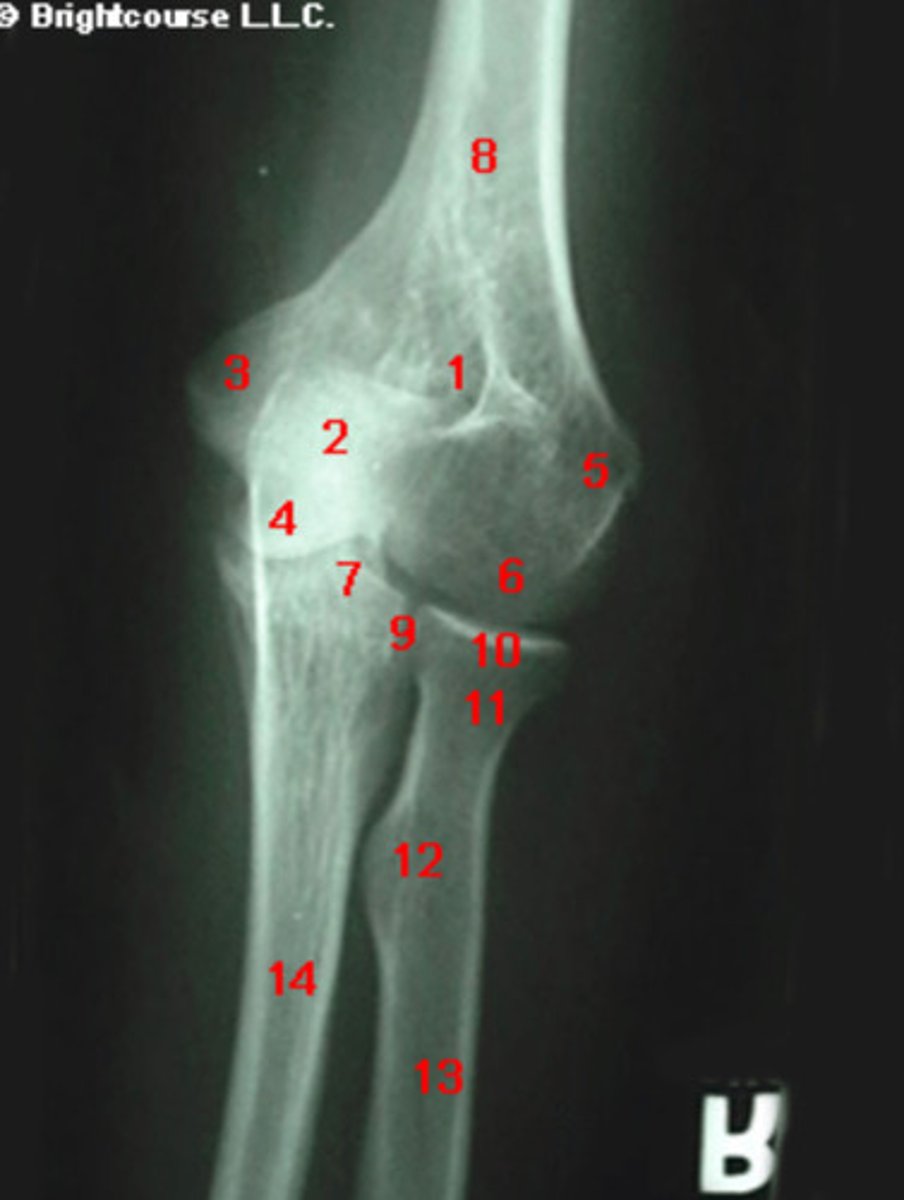

Coronoid process of the ulna

What structure is indicated by number 7?

What structure is indicated by number 1?

Lateral epicondyle of humerus

What structure is indicated by number 3?

Capitellum

What structure is indicated by number 6?

Radial neck

What structure is indicated by number 11?

Medial epicondyle of humerus

What structure is indicated by number 5?

Radial tuberosity

What structure is indicated by number 12?